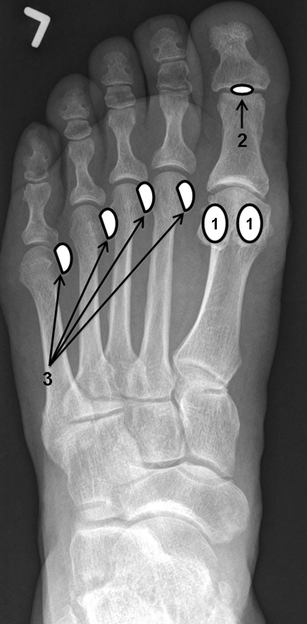

Sesamoids

Sesamoids of the foot. AP radiograph depicting the sites of hallucal (1), interphalangeal joint (2) and lesser metatarsal (3) sesamoids